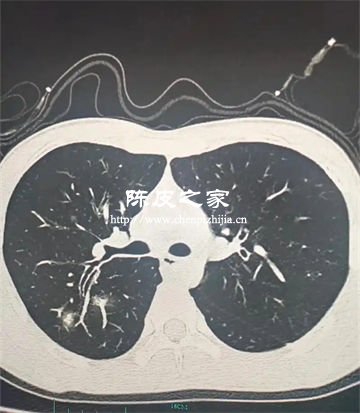

3.抑制氣道重塑與纖維化

PM2.5長期暴露會導致氣道杯狀細胞增生、黏液高分泌及纖維化,進而引發肺氣腫和小氣道重塑。陳皮多糖可減少氣道黏液分泌,抑制膠原沉積和纖維化進程,緩解PM2.5誘導的氣道結構改變。